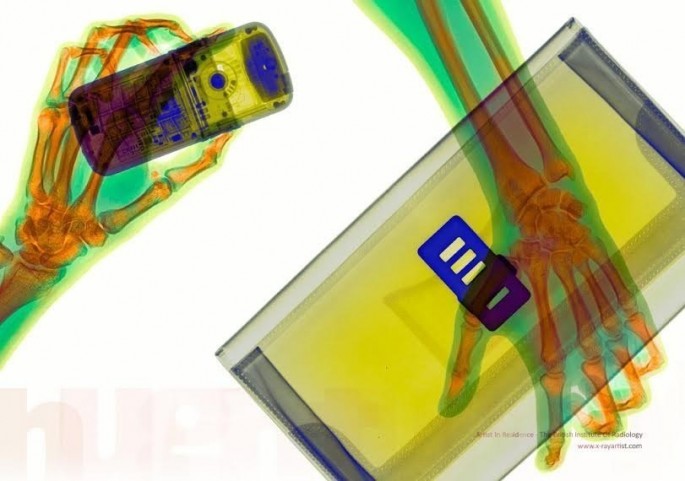

مجموعه ای بی نظیر تصاویر ایکس ری که شما را غافلگیر می کند.

به گزارش ایران خبر، معمولا از ایکس ری برای موارد پزشکی و علمی استفاده می شود و تصاویر خارق العاده ای تولید می کند .

در زیر تصاویری از بدن انسان در قالب ایکس ری را مشاهده می کنید.

در زیر تصاویری از بدن انسان در قالب ایکس ری را مشاهده می کنید.